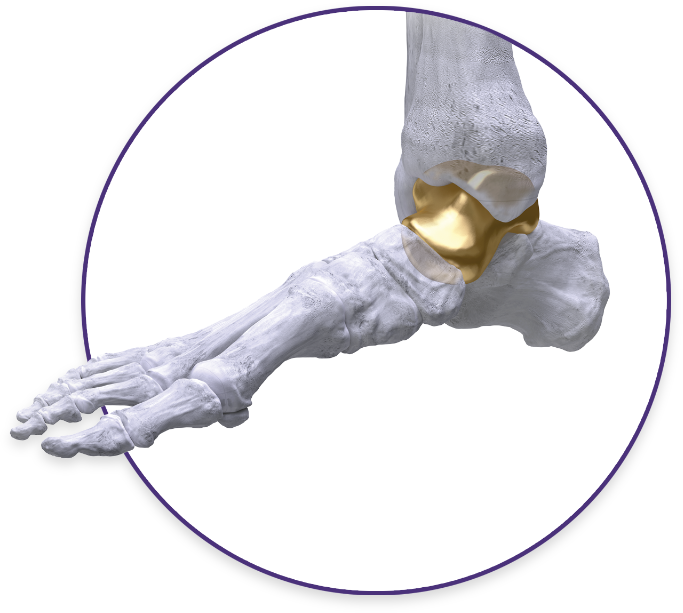

Total Talus Replacement

The Paragon 28 Patient Specific Talus Spacer is an alternative treatment option to fusion and amputation, and requires talus replacement surgery. During this procedure the native talus bone is removed and replaced with a 3D printed replica. This is considered a joint-sparing procedure, as it allows the patient to maintain motion of his/her ankle joint.

The Paragon 28 Patient Specific Talus Spacer is an additively manufactured, or 3D printed, patient specific implant that is designed and made individually for each patient using CT image data.

Total Talus Replacement

An alternative treatment option to fusion and amputation, the Paragon 28 Patient Specific Talus Spacer is indicated for avascular necrosis of the ankle and requires total talus replacement surgery.

The procedure is designed to relieve pain and preserve motion in the ankle joint by replacing the patient’s damaged talus with a 3D printed replica of his/her bone. Talus replacement surgery is considered a joint sparing procedure as it allows the patient to retain motion in the ankle joint.